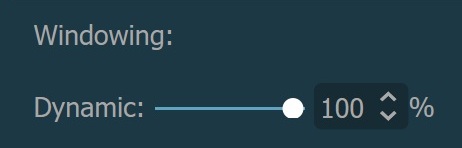

Alternatively, the percentage value of the maximum determined windowing range can be adjusted by using the Dynamic slider or the subsequent input field available in the windowing section when the dynamic mode is active.